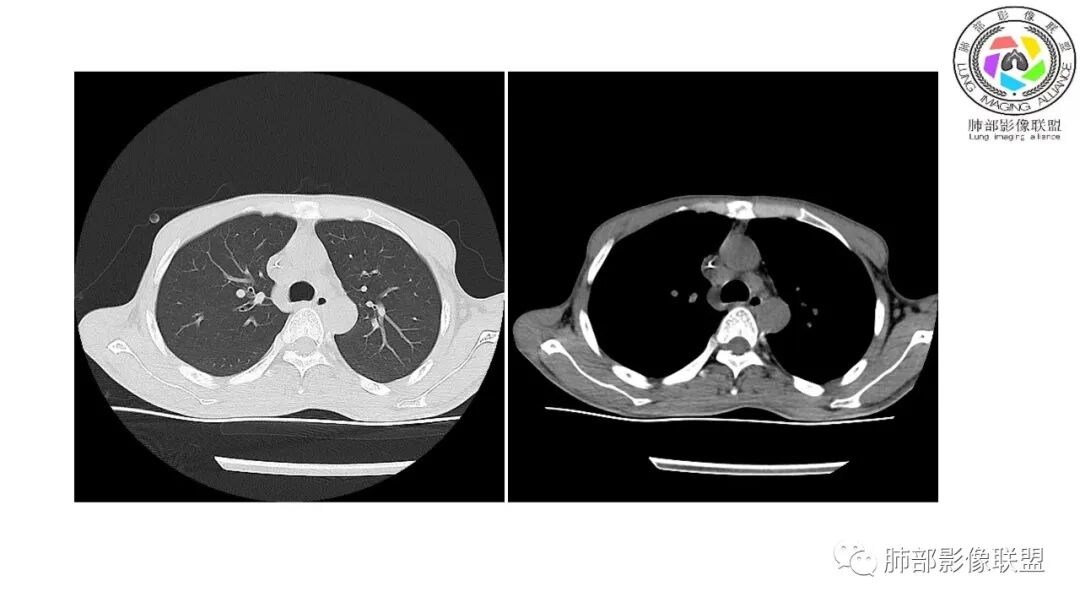

影像与临床:1.青年男性,HlV阳性,颜面部皮疹(未提供皮疹图像)、发热(高热),实验室CRP、PCT高,T-Spot阴性。2.右肺下叶空洞结节,壁厚不均,边界清楚,其内线状影,未见液平及钙化,未见卫星灶,纵隔淋巴结增大,双侧腋窝见增大淋巴结。心腔内低密度提示贫血可能。肝脾影增大,未见结节影及块影。腹膜后见多发增大淋巴结。

综合分析:本例肺部影像学改变并不具有特征性,空洞性病灶须与多种疾病鉴别,但年轻HIV阳性患者,高热,皮疹,肝脾增大,纵隔、腋窝、腹膜后见多发增大淋巴结等都强烈提示马尔尼菲篮状菌感染的可能性。